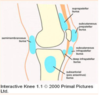

types of deformities associated with knee OA

varus (deviation of the distal component toward the midline; see image below

valgus deformity (deviation away from the midline)

fixed flexion deformity (in which the knee cannot be fully extended)